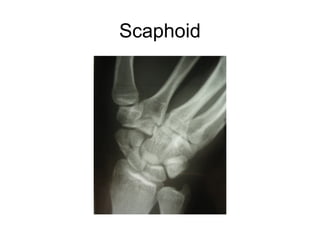

This document discusses several cases of scaphoid fractures in different patients. A 42-year-old female presented with carpal tunnel syndrome and wrist pain after a fall and was found to have a large cyst and fracture in her scaphoid bone. A 16-year-old male reported four months of painful wrist after a skateboarding injury. Imaging also showed a non-union in the wrists of a 42-year-old man bilaterally. Surgical treatment including open reduction and internal fixation with bone grafting was performed in some cases.